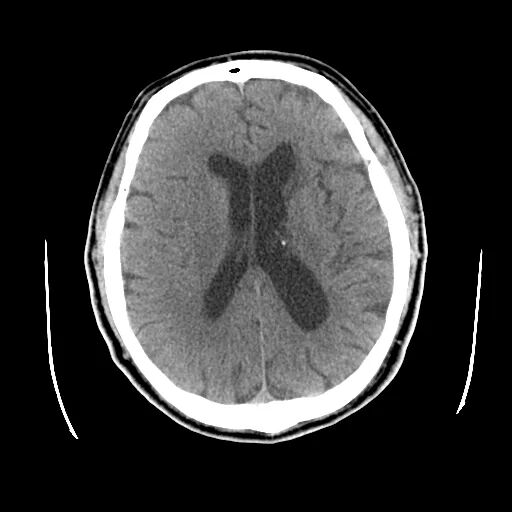

术前影像

颅脑CT:颅内多发腔隙性梗塞灶。